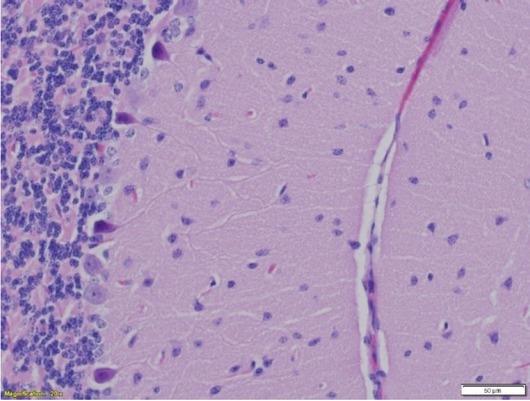

Microscopic view of the vacuolated neurons and glial cells (EMF group II) and appearance of interstitial oedema (oedema in neuropil) (H&E, 400×)

Histopathological lesions are shown in Figs 2–4. Shrinkage of pyramidal neurons, the presence of mild perivascular and perineuraloedema, and some vacuolation of neurons and glial cells derived from mouse great hemispheres were observed in EMF group I. Furthermore, reduction of Purkinje cells, vacuolisation of neurons and glial cells, and interstitial oedema in the cerebellum were also detected in EMF group II.